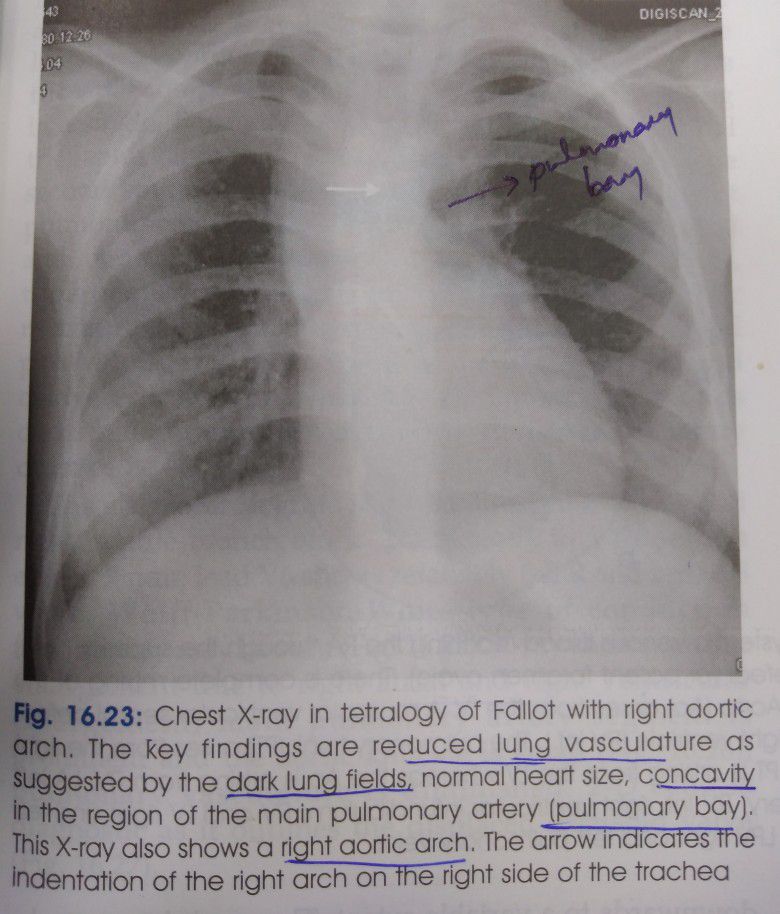

#VSD #PULMONARY INFUNDIBULAR STENOSIS #OVERRIDING OF AORTA #RIGHT VENTRICULAR HYPERTROPHY 1)Right ventricular hypertrophy due to pulmonary stenosis, causing increased right ventricular pressure and right to left shunt, till the pressure in both ventricles pressure balances. 2)More severity of pulmonary stenosis again cause right to left shunt. 3)P2 reduced in intensity due to stenosis. 4)loud A2 and ejection systolic murmur. 5)clubbing, cyanosis, prominent a wave, squatting posistion. 6)couer in sabot appearance of pulmonary artery 7)enlarged right aortic arch,ventricular hypertrophy 8)